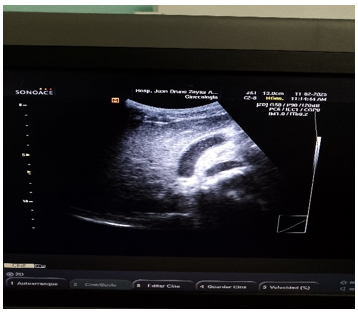

Ultrasonido Abdominal:

Hígado de tamaño normal, eco estructura homogénea, vías biliares no dilatadas, vesícula de tamaño normal con múltiples elementos alargados en su interior que impresiona parasitismo, conducto cístico tortuoso y dilatado hasta su unión con en el hepático común páncreas normal. Riñón izquierdo y derecho, ambos de tamaño y posición normal. Aorta y área de las suprarrenales normales, quiste en el ovario izquierdo sin repercusión.

Ultrasonido de Hemiabdomen superior (Confirmatorio).

Similar a la anterior, vesícula 78 x 19 x 20 mm con paredes normales y elementos ecogénicos alargados en suspensión que recuerda un parasitismo intestinal (Ver Figura 1, 2).

Figura 1

Figura 2

(Fuente propia de los autores)

La terapia antihelmíntica generalmente no se administra durante la fase pulmonar porque la eficacia de los fármacos contra las larvas en los pulmones es incierta. El uso de albendazol fue indicado como terapia complementaria por su excreción principalmente biliar; tanto en este caso como en otros pacientes como aparece informado en artículos médicos (5, 7). En el caso de Vargas-gallego. et al. (1) mostraron la importancia del estudio ecográfico para el diagnóstico de ascaridiasis errática hepato–biliar, presentándose formas ecográficas como el signo de ojo de buey que implica enrollamiento del parásito, el signo de la raya que es por una delgada raya sin tubo interno, y como en nuestro caso el signo del espagueti, cuando hay superposición longitudinal de parásitos en la vía biliar debido al enrollamiento de uno o varios áscaris.